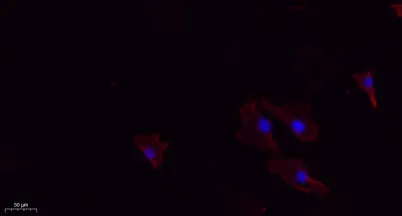

- Validated Applications: WB, IHC, IF, ELISA

- Dilution: Western Blot: 1/500 - 1/2000. IHC-p: 1:100-300 ELISA: 1/20000. IF 1:100-300 Not yet tested in other applications.